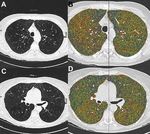

Fig. 1. Bilateral intermediate heteroge-

neous emphysema. Several potential

target zones become obvious by densi-

tometry. Lateral upper lobe on the

right side: (A) axial CT scan, (B) densi-

tometry, segment 6 on the right side:

(C) axial CT scan, (D) densitometry.